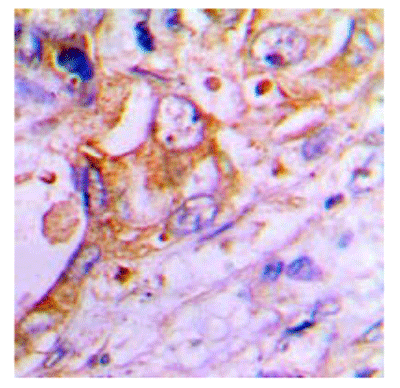

IHC (Immunohiostchemistry)

(Immunohistochemical analysis of Surfactant Protein C staining in human lung formalin fixed paraffin embedded tissue section. The section was pre-treated using heat mediated antigen retrieval with sodium citrate buffer (pH 6.0). The section was then incubated with the antibody at room temperature and detected using an HRP conjugated compact polymer system. DAB was used as the chromogen. The section was then counterstained with haematoxylin and mounted with DPX.)